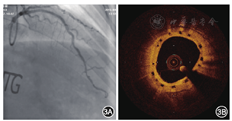

2016年4月27日行冠状动脉造影检查,结果显示:左主干正常;左前降支近段支架通畅,无再狭窄,中远段狭窄程度为30%;左回旋支远段狭窄程度为70%;右冠状动脉近远段狭窄程度为20%~30%(图3A)。OCT检查结果示左前降支近段支架内膜覆盖良好,平均管腔面积为5.78 mm2,最小管腔面积为4.86 mm2,斑块负荷为30.6%,新生内膜面积为2.84 mm2(图3B)。术后口服阿司匹林肠溶片100 mg(每天1次),替格瑞洛片90 mg(每天2次,至2016年5月11日),阿托伐他汀钙片20 mg(每晚1次)。